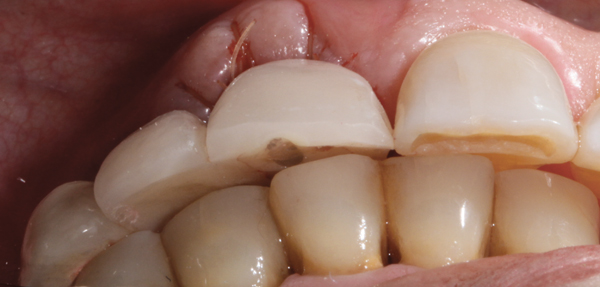

Fig 14. At 4 months following implant placement, the tissue position should be evaluated. Use of the narrowed emergence profile helped to produce increases of ~ 1 mm of soft tissue in this 82-year-old patient.

Figure 14